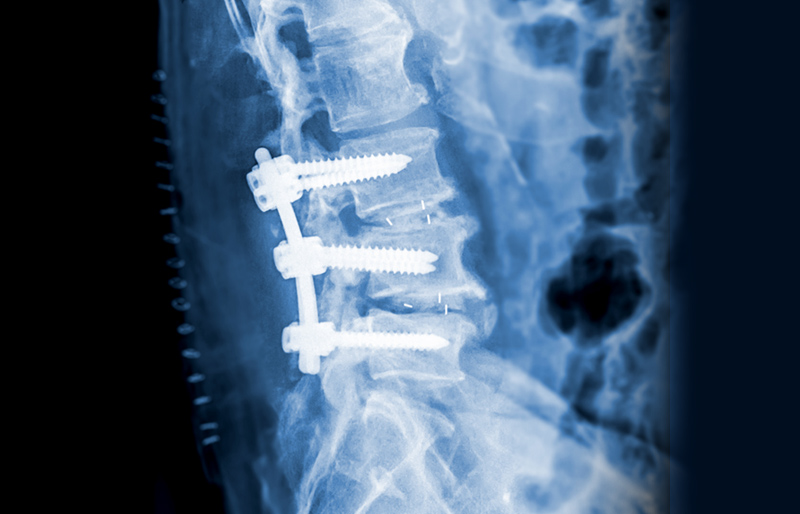

ôÃß ¿òÁ÷ÀÓÀÇ Á¦ÇѰú ±×·Î ÀÎÇÑ Ã´Ãß °üÀýÀÇ ÀüüÀûÀÎ ÅðÇàÈ­

¼ö¼ú ºÎÀ§ÀÇ À¯Âø°ú ÅëÁõ Áõ°¡

Ãß°£ÆÇÀÇ ¾àÈ­ ¹× ÅðÈ­ ¼Óµµ Áõ°¡